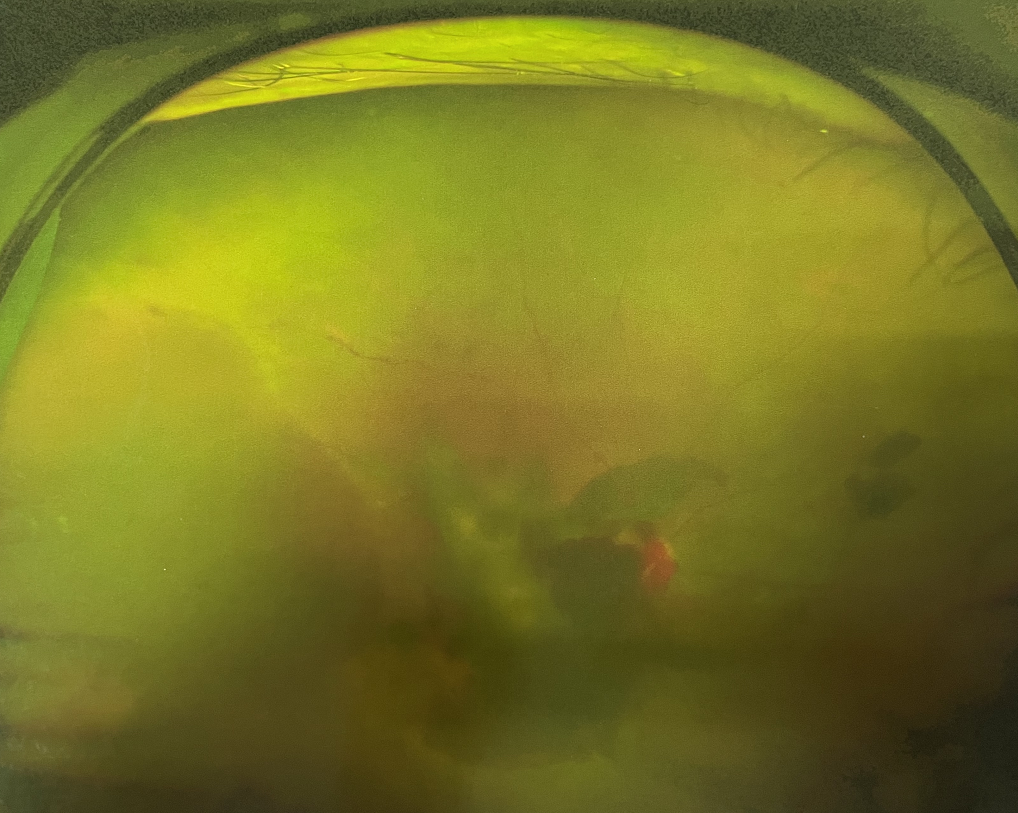

四十多歲的王女士,患高血壓病及Ⅱ型糖尿病多年,一直靠藥物控制血壓和血糖。去年,王女士右眼看手機(jī)時(shí)感覺(jué)視物不清,總感覺(jué)眼前有一層霧,視力也逐漸下降,于是來(lái)廈門大學(xué)附屬?gòu)B門眼科中心就診。

眼底病??茝埿』⑨t(yī)生檢查后,診斷王女士為“雙眼玻璃體積血、雙眼糖尿病視網(wǎng)膜病變V期”。(V期即5期,纖維增生期,出現(xiàn)纖維膜,可伴視網(wǎng)膜前出血或玻璃體出血。)

右眼術(shù)前